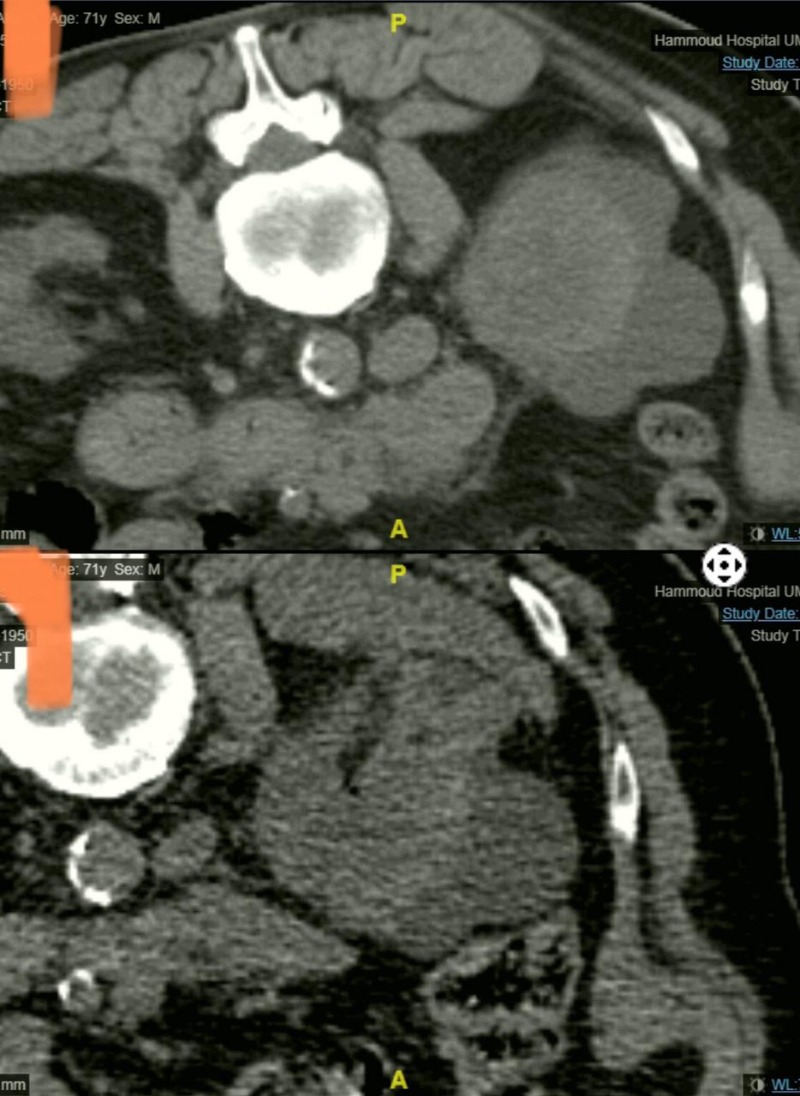

إنجاز طبي جديد في مستشفى حمود الجامعي لأول مرة في الجنوب، عبارة عن علاج ورم ضخم في الكلية مكون من كتلة سرطانية تتخطى ال٦ سنتم بالتقنية الحديثة Cryoablation Of Tumor Under CT

وهي تقنية تجميد وقتل الأورام السرطانية الخبيثة دون إجراء عملية جراحية ودون آلام.

قام بإجراء العملية الدكتورعلي كنج، رئيس قسم الأشعة في مستشفى حمود الجامعي، لمريض في العقد السادس من عمره من خلال تخدير موضعي حيث تمكن المريض من مغادرة المستشفى في اليوم الثاني.